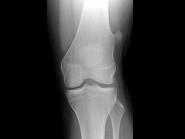

问题 女,39岁。发现左大腿下段后部有一肿块,质较硬,无明显疼痛感觉,结合所提供的图像,最可能的诊断是?(?)

选项 A.软骨肉瘤 B.软骨瘤 C.骨肉瘤 D.骨软骨瘤 E.骨瘤

答案 D